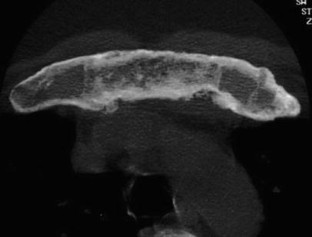

SAPHO: syndrome or concept? Imaging findings

The SAPHO syndrome was a term coined to include a variety of musculoskeletal disorders associated with skin conditions, mainly palmoplantar pustulosis and acne conglobata. It is more correctly a spectrum which includes the following: skin lesions, osteoarticular manifestations of synovitis hyperostosis and osteitis affecting particular target sites, and·a clinical course marked by relapses and remissions. The major sites of involvement are the anterior chest wall, the spine, long bones, flat bones, and large and small joints. The distribution and severity of involvement varies from the adult to the pediatric form of chronic recurrent multifocal osteomyelitis (CRMO). The diagnosis of SAPHO syndrome is not difficult when the typical osteoarticular lesions are located in characteristic target sites. The diagnosis is more difficult if atypical sites are involved and there is no skin disease.